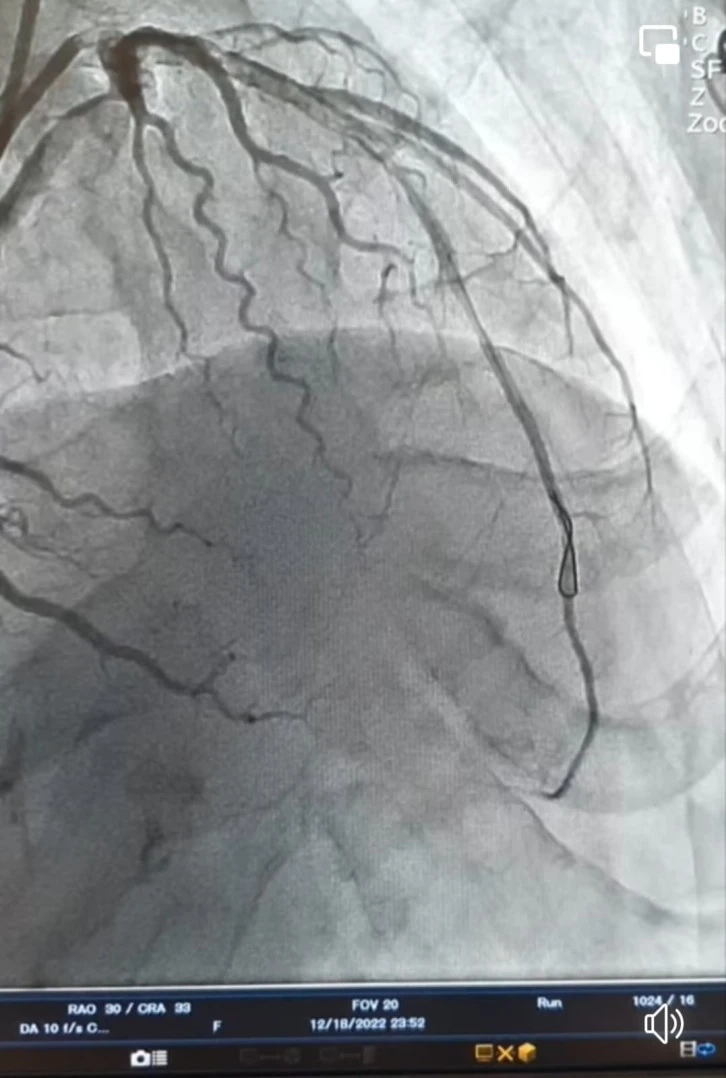

Hastanın kalp damarları Culotte stentleme tekniği ile açıldı

Kilis Prof. Dr. Alaeddin Yavaşca Devlet Hastanesi acil servisine kalp krizi şikayeti ile getirilen 55 yaşındaki bir erkek hastanın kalp damarları başarılı bir opersayon ile açıldı.

"Kalp krizi ile acil angiografi yaptığımız 55 yaşındaki erkek hastanın kalp damarlarını Culotte stentleme tekniği başarılı bir şekilde açtık" diye konuştu.